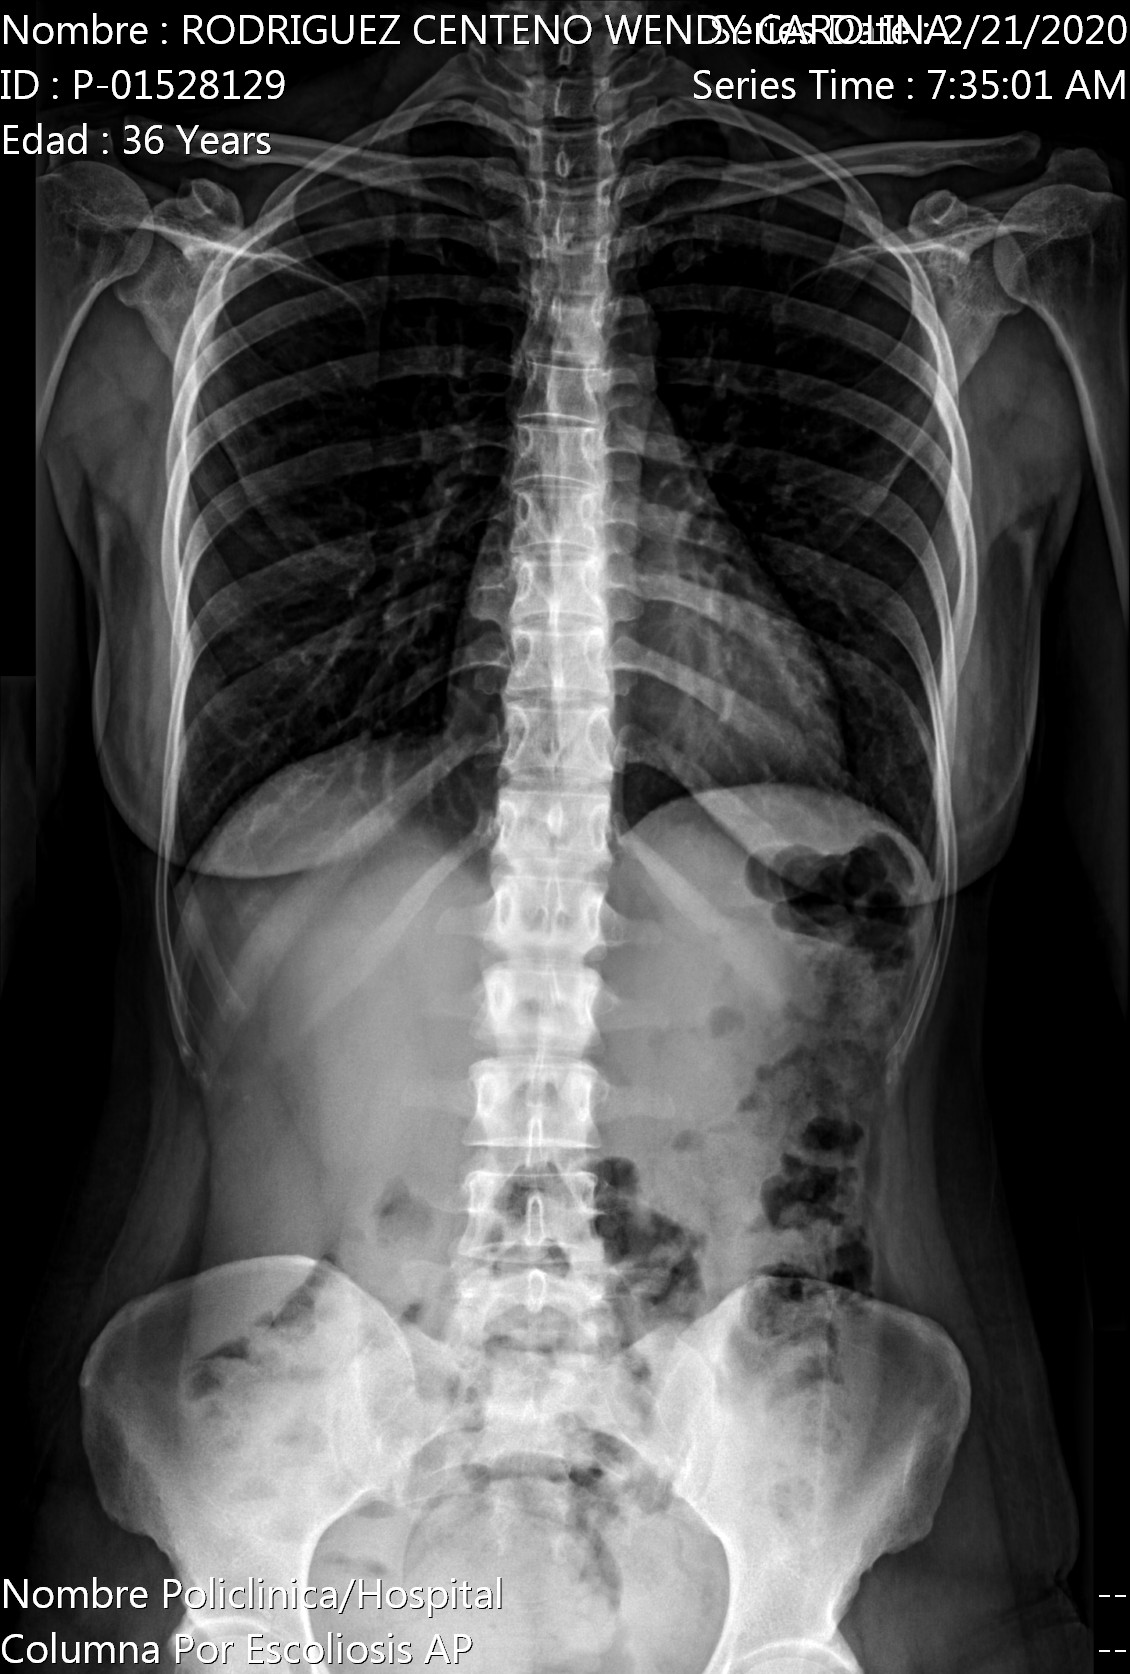

Ho un forte dolore al bacino. Il dolore è più acuto quando devo alzarmi da una sedia e non posso camminare se non lentamente per il forte dolore.

Allego i raggi x appena fatti.

Buongiorno signora. Alle rx non si vede nulla di particolare. Dovrebbe sentire uno specialista quando questa crisi sanitaria sarà risolta. Cordiali saluti